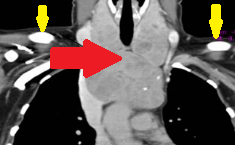

CT θώρακος-τραχήλου. Κόκκινα βέλη — Πολύ μεγάλη οπισθοστερνική βρογχοκήλη. Κίτρινα βέλη — Κλείδες (Ευγενική παραχώρηση Dr. V. Penopoulos)